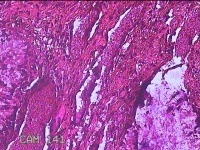

性别

女

年龄

32岁

临床诊断

左耳后肿物

一般病史

左耳后无痛性肿物2周。

标本名称

大体所见

灰白粉红色片状肿物0.7x0.5x0.2cm一个,表面光滑。